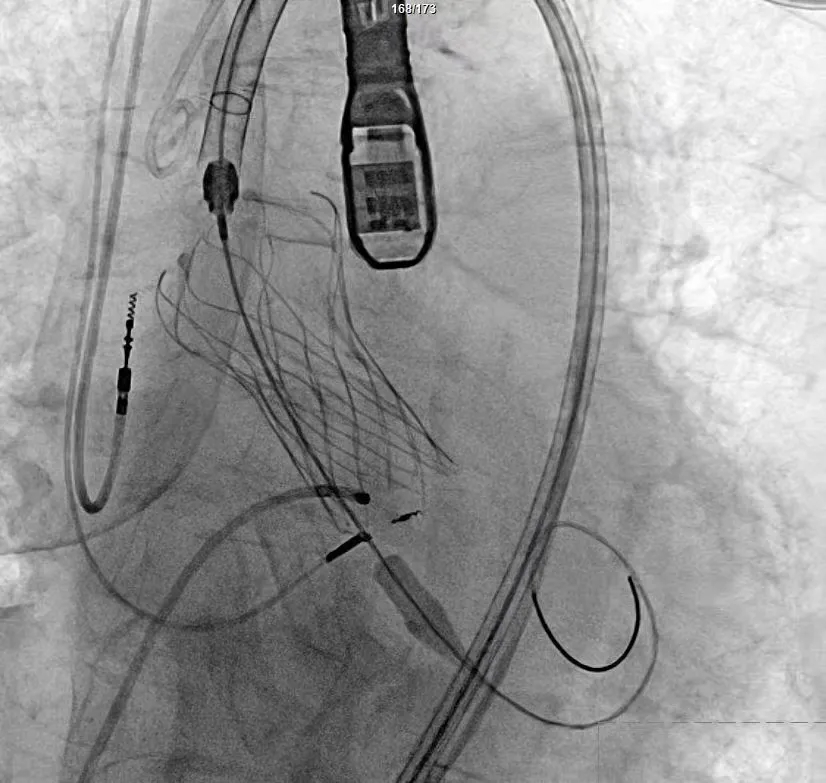

▶ 微创入路精准定位:采用新一代可回收瓣膜系统,通过股动脉入路完成精准植入,术中应用3D打印模型辅助导航,确保手术路径精准;

▶ 双影像实时护航:结合经食道超声(TEE)与数字减影血管造影(DSA)双影像融合技术,动态调整导管位置,误差控制在毫米级;

手术过程严谨有序:经术前精准评估与周密准备,团队成功送入预先装载的自膨式支架瓣膜输送系统,顺利完成过弓、跨瓣操作;经造影定位后,在180bpm快速起搏下精准释放瓣膜。瓣膜释放后,术中实时超声显示根部瓣架形态良好、启闭正常,瓣叶中心及瓣周未见反流;造影显示瓣膜位置满意、形态良好,冠脉显影清晰,入路血管无损伤,历经90分钟后,手术圆满成功。

术中影像